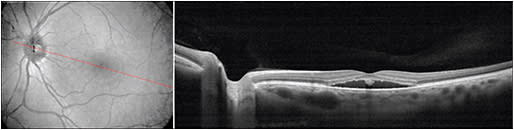

The corresponding SLO image has a 12-fps frame rate and 40° x 30° angle of view. All of the images were taken centered at the fovea, as well as at an extrafoveal location when the CSC was located in the periphery (Figure 3).

Figure 3. OCT Nidek RS-3000 Adanced. Central serous chorioretinopathy in the right eye of a 48 year-old Caucasian man.